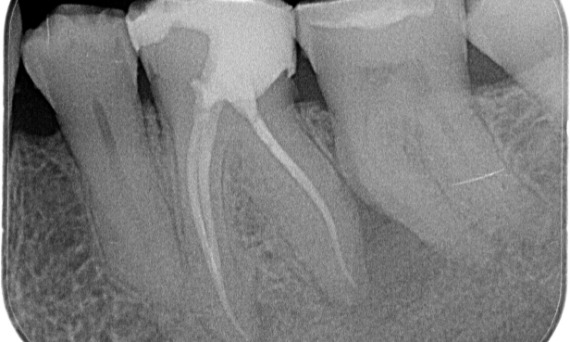

Antes: Radioluscência periapical associada principalmente à raiz distal e perda da lâmina dura na raiz mesial.

Depois: TruNatomy foi escolhido neste caso para permitir uma abordagem alavancada da cárie dental e um foco na preservação da dentina pericervical, especialmente no aspecto mesial, onde o dente teve uma restauração mais mínima.

Dr. Jonathan Cowie (especialista em endodontia)

Bath, Reino Unido